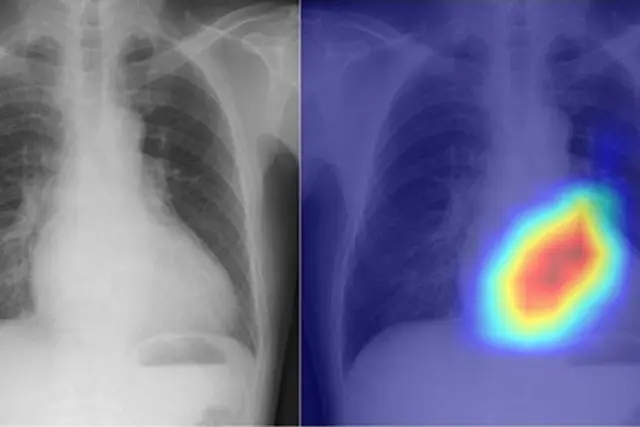

據《柳葉刀數字健康》雜誌發表的研究論文,來自大阪市立大學的研究人員招募了一個深度學習的人工智能模型,該模型可以將簡陋的胸部X光檢查轉變為一個更有力的心臟問題診斷工具,能夠為心臟功能評估和疾病檢查提供更快速和準確的方法。

基於此,研究人員寄希望於通過深度學習的人工智能模型將X光胸透轉化為更好的診斷工具。所謂深度學習,是人工智能使用的一個過程,教計算機以模仿人腦的方式處理數據。該模型可以識別圖片、文本、聲音和其他數據中的複雜模式,從而產生準確的洞察力和預測。

在對該模型的訓練過程中,研究人員從四個機構的16946名患者那裏獲得的與22551張超聲心動圖相關的胸部X光片,由此對模型進行深度學習訓練。其中,X光片被設定為輸入數據,超聲心動圖被設定為輸出數據,模型被訓練為學習連接兩個數據集的特徵。在對深度學習模型進行測試時,研究人員發現,它可以精確地將六種類型的瓣膜性心臟病分類。